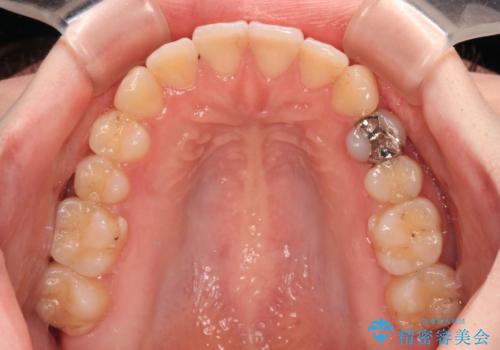

開咬と前方に飛び出した前歯 インビザラインによる矯正治療

- 上下前歯の非接触と叢生を気にして来院された患者様です。

開咬の改善はインビザラインの最も得意とするところであるため、インビザラインを用いて矯正治療を行うこととしました。

舌の突出癖改善のトレーニングをしっかりと行っていただき、上下前歯が接触する咬み合わせを達成することができました。